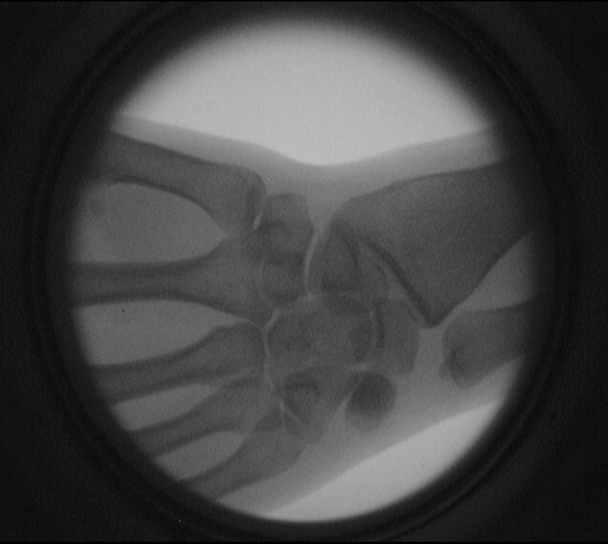

電熱絲和電熱絲的接口 手關節透視圖